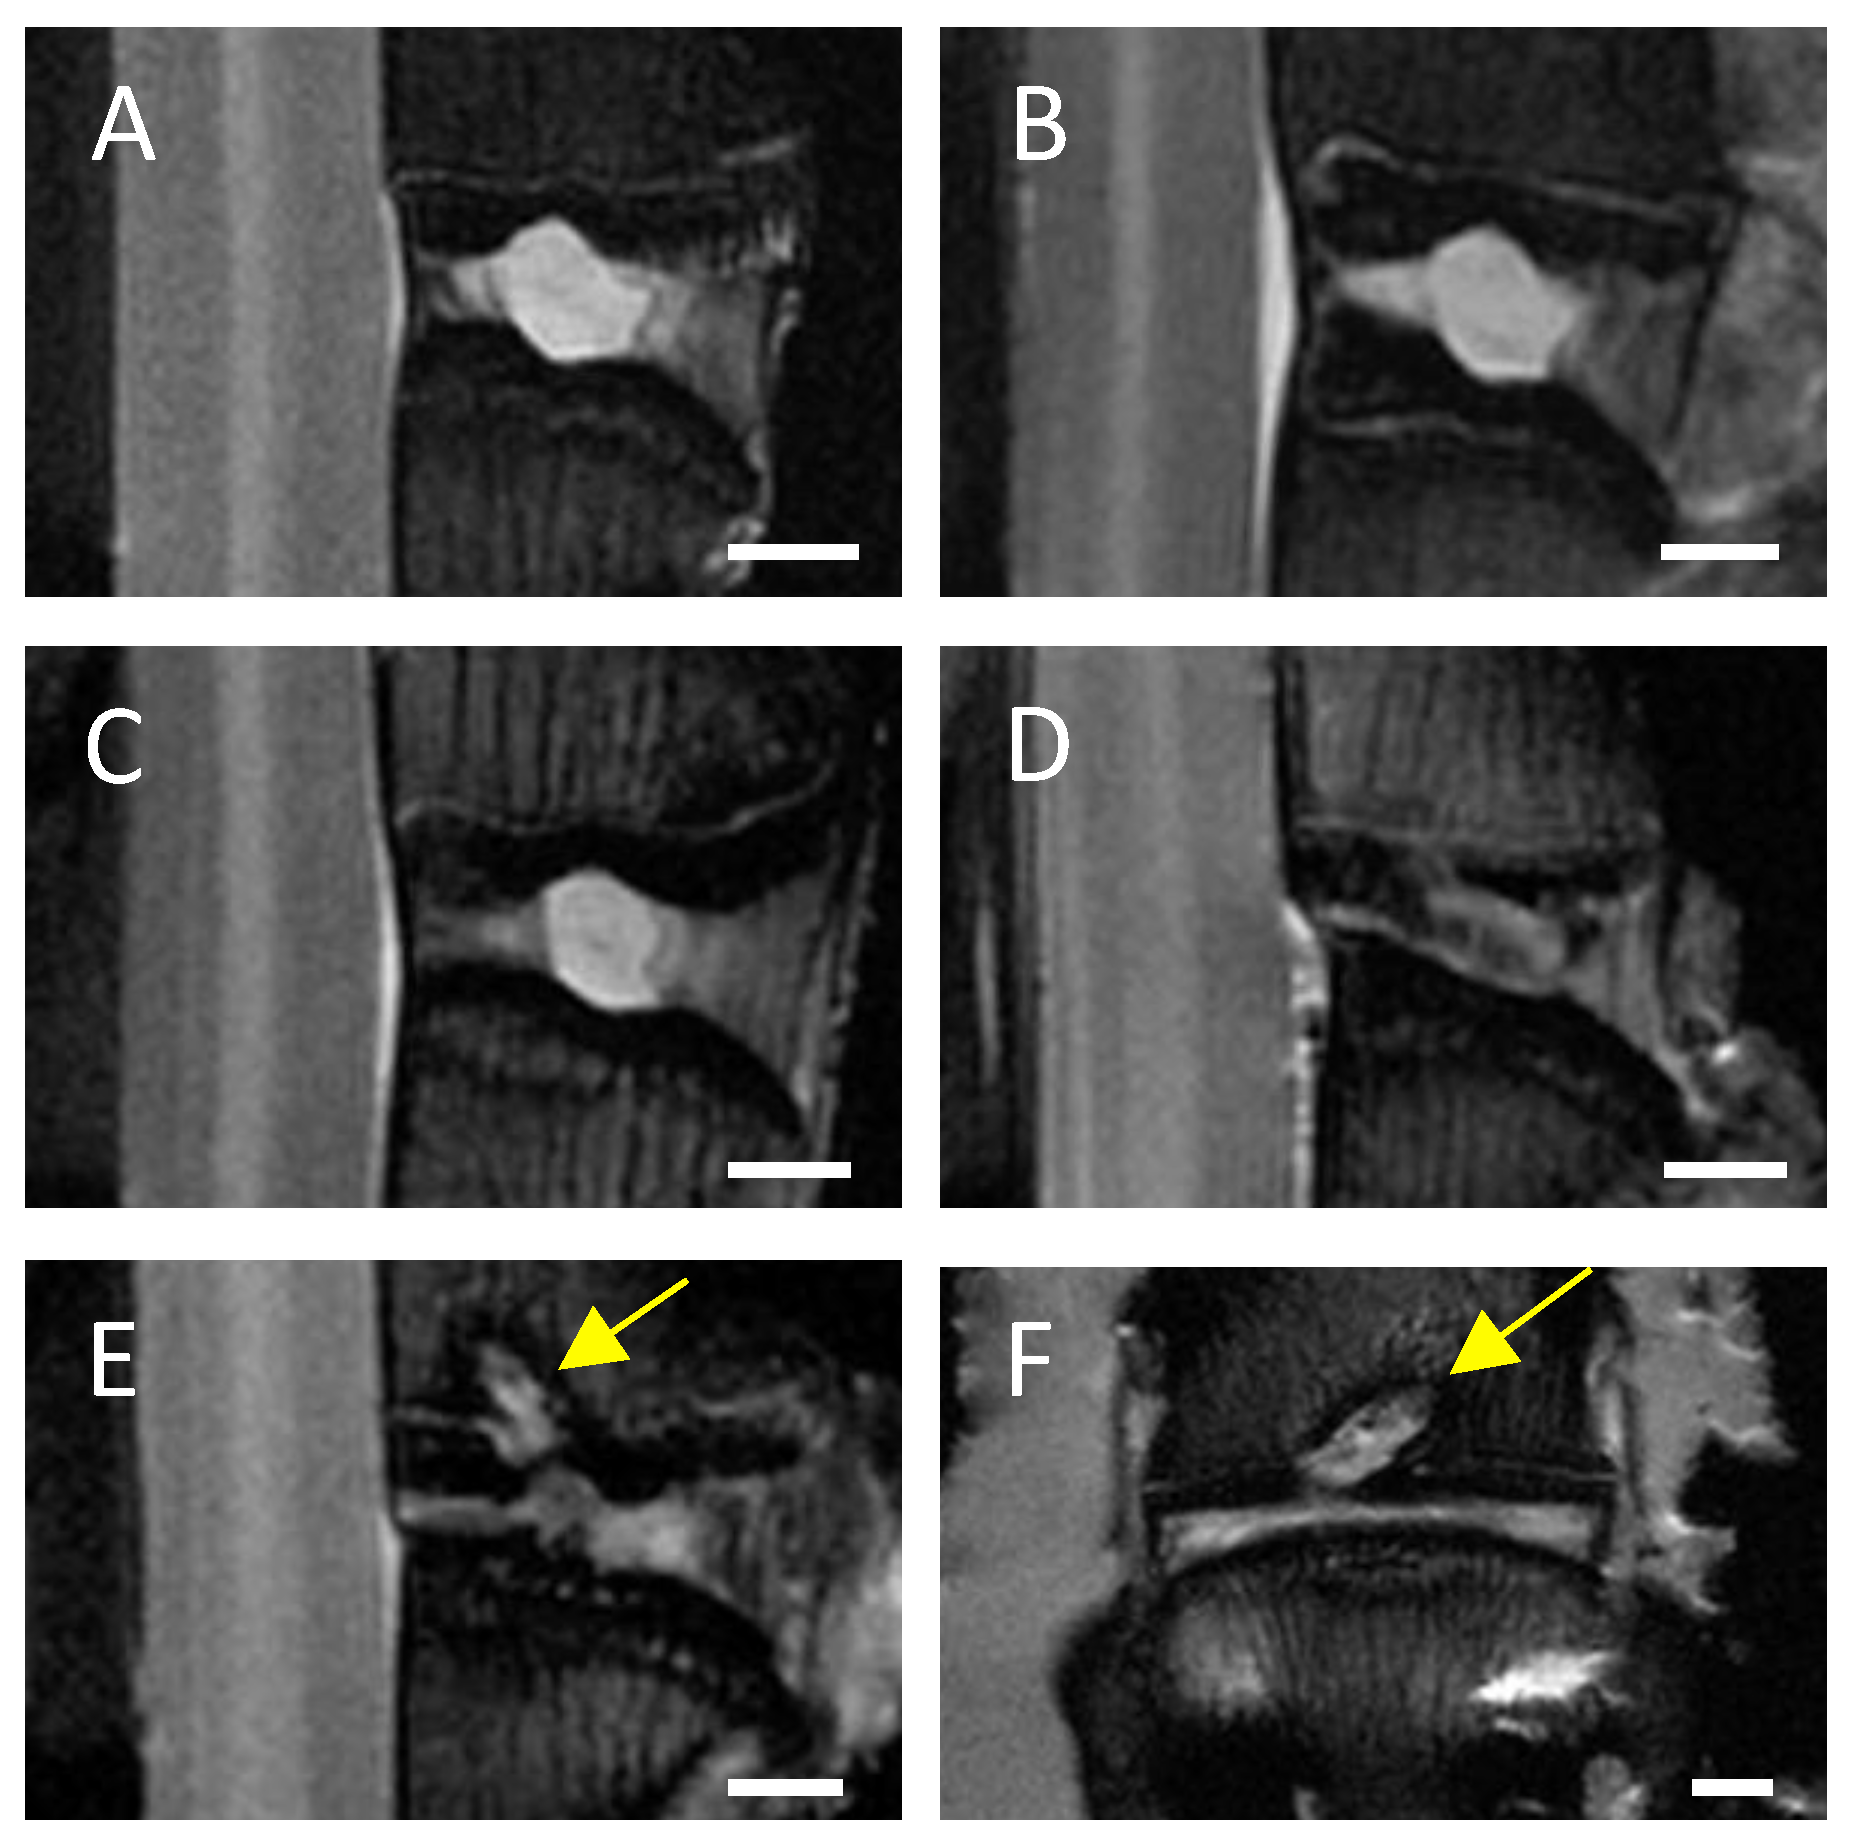

In MRI scans of untreated control IVDs and needle-punctured IVDs no or only minimal signs of degeneration, such as an inhomogeneous IVD structure with slight grey bands, were visible in both C6+/− and C6−/− rabbits (Figure 2A,B). Based on visual evaluation of the MRI scans, EP-drilled IVDs generally appeared more degenerated; 5 of 13 analyzed IVDs treated with EP drilling were clearly degenerated (C6+/− n = 3 of 7, C6−/− n = 2 of 6; Figure 2C) and exhibited an inhomogeneous IVD structure with the loss of signal intensity. Another 4 of the 13 analyzed EP-drilled IVDs furthermore exhibited signs of severe degeneration, such as a grey to black inhomogeneous IVD structure with drastically reduced signal intensity and unclear or even lost distinction between AF and NP (C6+/− n = 2 of 7, C6−/− n = 2 of 6; Figure 2D). In a total of 5 animals, the drilling channel within the adjacent vertebral bodies of the IVDs treated with EP drilling was visible in the MRI images 12 weeks after surgery (C6+/− n = 1 of 7 [14%], C6−/− n = 4 of 6 [67%]; see Figure 2E,F).

Figure 2.

Representative central MRI images. Exemplary midsagittal MRI images of lumbar rabbit IVDs exhibiting (A) no signs of degeneration, signs of (B) mild degeneration (inhomogeneous IVD structure with slight grey bands), (C) clear degeneration (inhomogeneous IVD structure and loss of signal intensity), and (D) severe degeneration (grey to black inhomogeneous IVD structure, drastically reduced signal intensity, and unclear distinction between AF and NP). Exemplary (E) midsagittal and (F) midcoronal MRI scan of an EP-drilled IVD with visible drilling channel (marked by yellow arrows). Scale bar: 2 mm.